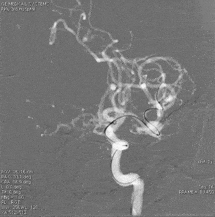

术前影像:术前正侧位。

术前影像:术前工作位。

三维重建:显示左侧MCA分叉部未破裂动脉瘤,约8.2mm*8.6mmm,瘤颈3.8mm,顶端有子瘤。

术前影像学检查:术前正侧位。

术前工作位与三维重建:显示右侧MCA分叉部未破裂动脉瘤,6.9mm*7.2mm,瘤颈7.4mm。该病例之困难在于M1迂曲成袢。